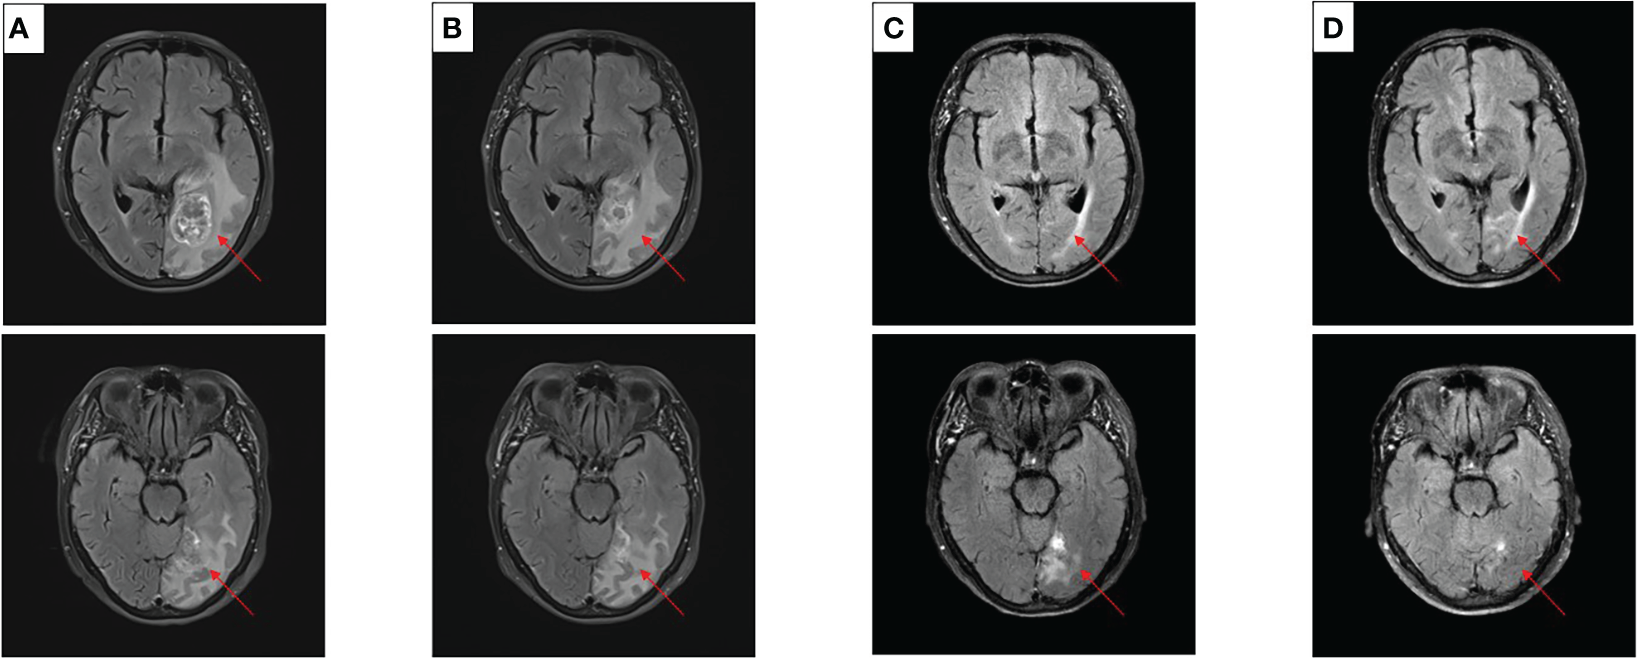

After experiencing dizziness and headache, the patient was reexamined by brain MRI on 19 January 2021, which revealed a new brain metastasis in the left occipital lobe (Figure 3A). The patient refused radiotherapy, chemotherapy, and immunotherapy, and started oral dacomitinib treatment with a dose of 30 mg daily. After several days, the patient’s neurological symptoms were significantly relieved. The patient underwent MRI 2 months later, and found that the lesion was significantly reduced, the efficacy achieved partial response (PR) (Figure 3B), and follow-up MRI at 4 and 6 months showed that the lesion continued to shrink and almost disappeared (Figures 3C, D). The patient continued to receive dacomitinib until new right parietal lobe brain metastases were identified on 23 June 2022 (the cutoff day, Figures 4A, B), and the progression-free survival (PFS) was 17 months (Figure 5). No obvious adverse reactions have been observed during the patient’s medication.

Figure 3

Craniocerebral MRI about clinical response to dacomitinib therapy at different times. (A) Baseline before dacomitinib treatment. (B) Brain metastases partial response (PR) after 2 months. (C) Brain metastases PR after 4 months. (D) Brain metastases PR after 6 months.